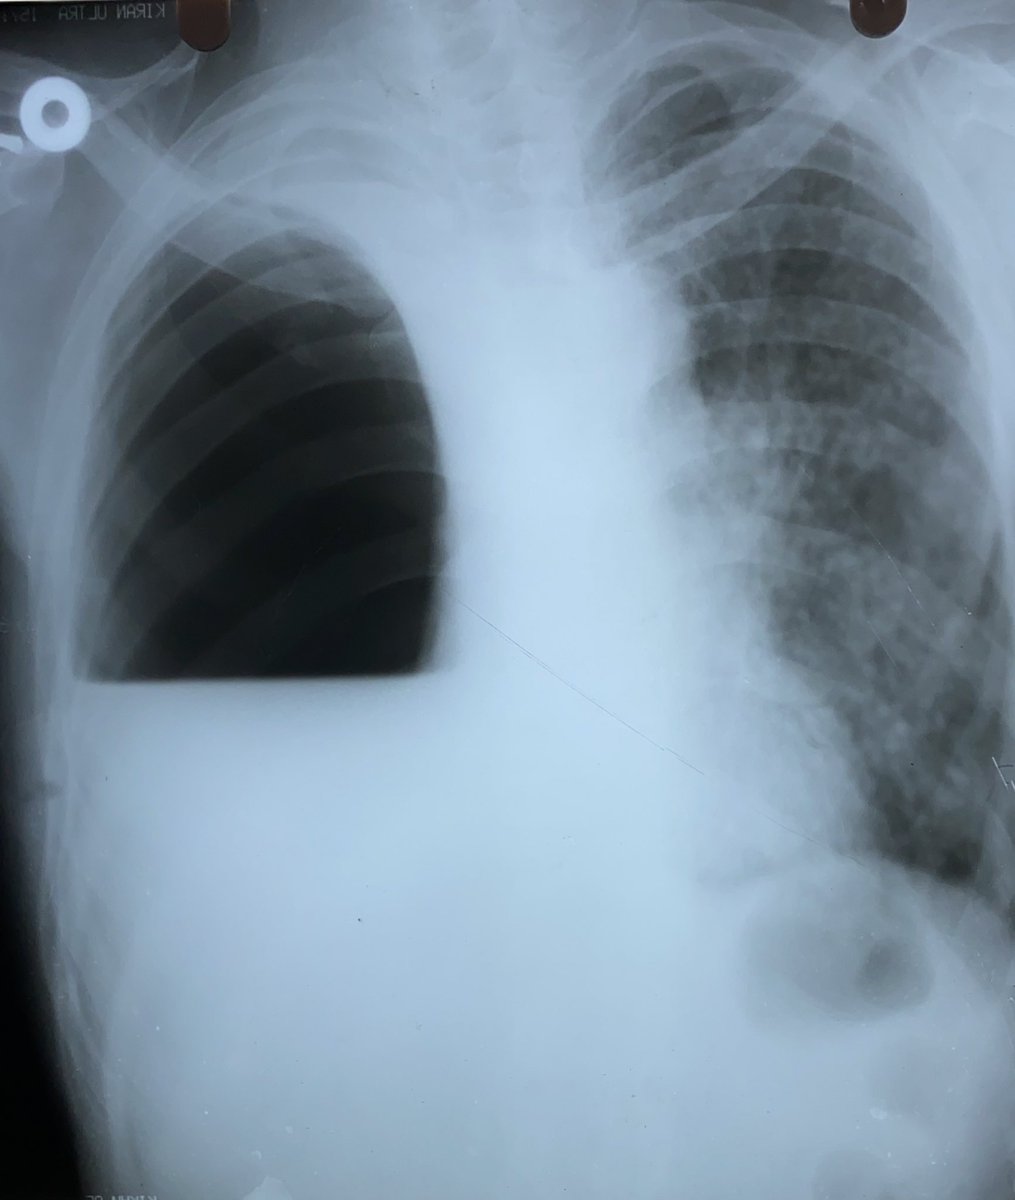

His CXR showed this 👇 Image

On probing and asking many times is when the poor relatives told me that they were driven away from the govt hospital without any treatment or diagnosis, after doing a 🩻 showing this Image